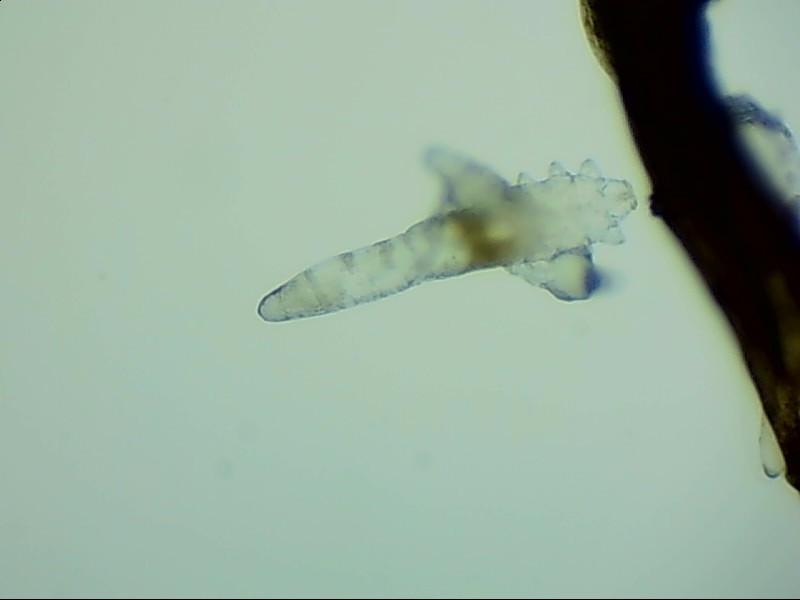

蠕形螨完全長大也只有0.1-0.2毫米,因此肉眼難以看到它們,只有在電子顯微鏡下我們才能看到睫毛根部的一只只蠕形螨。這些螨蟲每天都很活躍,且繁殖速度極快,完成一代生活史僅需大概15天。

螨蟲無所遁形,螨蟲鏡檢:

螨蟲鏡檢主要是通過顯微鏡觀察,它能無死角放大你的睫毛,讓螨蟲無處可躲。

在檢查的時(shí)候,醫(yī)生要在每個(gè)眼瞼上拔出幾根比較典型的睫毛,然后放在光學(xué)顯微鏡下,尋找有沒有螨蟲,同時(shí)觀察螨蟲的數(shù)量多少。

如果任意一個(gè)眼瞼上螨蟲數(shù)量較多,再加上你的眼睛有局部癥狀,后續(xù)就需要進(jìn)行相應(yīng)的治療了。